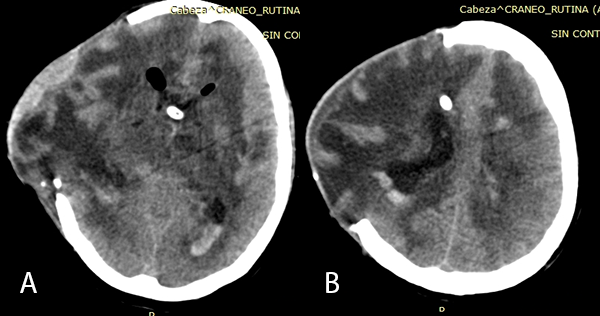

Posteriormente, el paciente persiste con deterioro clínico llegando a una escala de Vellore de IV(5) (en el examen físico presentaba signos de decorticación y pupilas anisocóricas); por falla de DVE se decide colocar un nuevo sistema de DVE, evidenciándose en la TEM control asimetría en los ventrículos (Imagen 3), motivo por el cual el paciente es sometido a una endoscopía para fenestración de septum pellucidum.

Imagen 3: (A), (B), (C) TEM cerebral sin contraste cortes axiales previa a la fenestración endoscópica, se evidencia hidrocefalia asimétrica post colocación de DVE en el cuerno frontal izquierdo.

Se realizó la neuroendoscopía utilizando una óptica de 0 grados, de 30 cm. ingresando por el lóbulo frontal derecho. Inmediatamente al ingreso de la óptica se evidenciaron múltiples adherencias intra ventriculares. El foramen de Monro se encontraba parcialmente obstruido por una adherencia, además el epéndimo presentaba coloración amarillenta y las adherencias se encontraban difusamente en los ventrículos. Se intentó realizar una extracción de las membranas, pero se encontraban adheridas firmemente a las paredes ventriculares. (Imagen 4). Se realizó la fenestración del Septum Pellúcidum, con colocación de una nueva DVE, por lo que el paciente presentó mejoría clínica e imagenológica (Imagen 5).

Imagen 5: (A) y (B) TEM cerebral sin contraste en cortes axiales post fenestración y colocación de nuevo DVE: se evidencia disminución de la asimetría ventricular y disminución de protrusión por defecto óseo craneal.

La hidrocefalia en pacientes con TBC meníngea es más común de tipo comunicante (aproximadamente el 80%).(11) En el caso del paciente, probablemente las adherencias intraventriculares y la obliteración parcial del foramen de Monro hayan causado una hidrocefalia asimétrica y obstructiva.